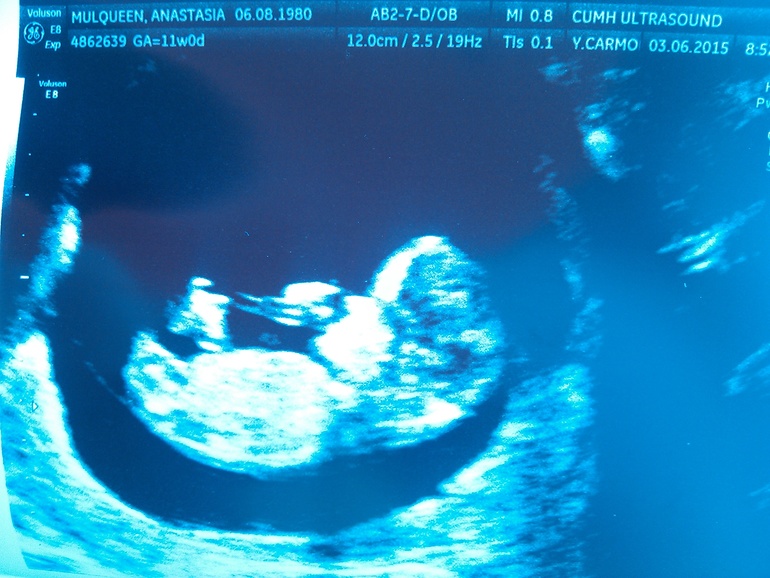

УЗИ, КТГ, доплер12я неделя, а значит первый триместр позади! Ура! Сегодня были на втором УЗИ, видели малыша)... Он заметно подрос, изменился внешне, и вообще стал выглядеть как маленький человечек) Демонстрировал нам во всю, что его жизнедеятельность у меня в животе протекает активно.. За то короткое время, что мы за ним наблюдали, он успел подрыгать всеми конечностями, мне даже показалось сосал пальчик, а в конце стал потягиваться, выгибая позвоночник) Надоело ему лежать на одном месте, видно. Так и написали о нем в комментариях к УЗИ, активный)

Сказали, что все нормально у нас, я спросила, какого размера малыш, оказалось, 4.55 см) А я думала, он больше уже.. Но, ничего, сказали, нормальный размер) А муж, говорит, а ты, что прям большого ребенка хочешь?) Нее..его ж еще родить умудрится надо будет) Порадовалась, что активный, так и смотрела бы на него вечно...Буду ждать с нетерпением следующего раза..Кстати, пол нам не сказали, маленький срок еще.